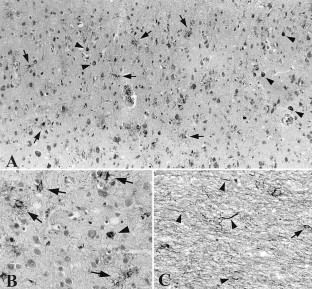

We report a Japanese autopsy case of progressive supranuclear palsy (PSP). The male patient was 74 years old at the time of death. At age 64, he developed non-fluent aphasia that progressed slowly over 8 years, eventually associated with behavioral abnormality, postural instability, and dysphagia at 2 years prior to his death. Magnetic resonance imaging of the brain at age 73 demonstrated marked atrophy of the frontal lobes, particularly on the left side. Neuropathological examination revealed the typical pathology of PSP: loss of neurons, gliosis, occurrence of neurofibrillary tangles, oligodendroglial coiled bodies, and tuft-shaped astrocytes in the frontal cortex, associated with argyrophilic threads in the underlying white matter, in the basal ganglia, including the thalamus, globus pallidus, and subthalamic nucleus, and in the brainstem nuclei, including the substantia nigra, pontine nucleus, and inferior olivary nucleus. No astrocytic plaques or ballooned neurons were observed. Protein analysis revealed accumulation of hyperphosphorylated tau of 68 and 64 kDa consisting of the four repeat tau isoforms. We conclude that the present case represented PSP with an 8-year history of primary progressive aphasia (PPA). Although focal cortical symptoms in PSP are rare or absent, we should keep in mind the possibility of atypical PSP in which cortical pathology is predominant, particularly in the frontal lobe, and could result in PPA.